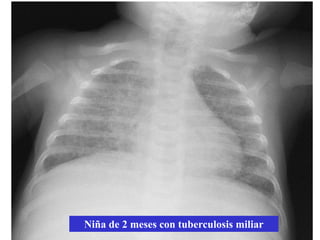

Rx tórax

• Niño: primoinfección. Patrón muy variable

– Adenopatías hiliares ó mediastínicas: muy

llamativas vs. infiltrado

– Hiperinsuflación segmentaria y/o atelectasia

(enfisema obstructivo <2 años)

– Consolidación alveolar ó intersticial

– Derrame pleural

– TB miliar

Imagen miliar           Tuberculosis, hongos